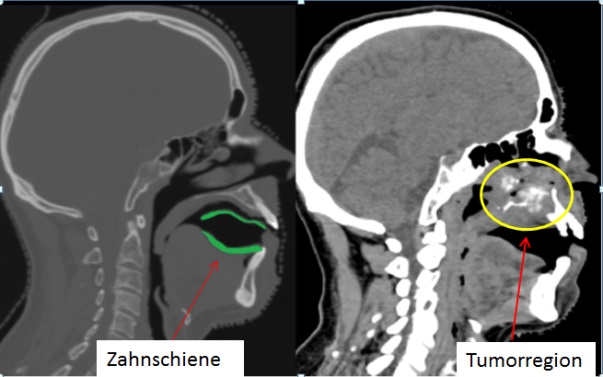

Bei Behandlungen, die auch den Oberkiefer einbeziehen und bei denen Strahlung am Gaumen ankommt, haben wir gemeinsam mit einem Zahnarzt aus Mühlheim eine individuelle Zahnschiene entwickelt, mit deren Hilfe sich die Zunge gezielt schonen lässt. Um die Zunge zu schützen, sollte – das haben unsere Physiker ermittelt – der Mund etwa zwei Zentimeter weit geöffnet sein. Statt eines unbequemen, wackeligen Bisskeils kann für solche Patienten eine individuelle Schiene angefertigt werden, die an Ober- und Unterkiefer fixiert wird und quasi schützend über der Zunge liegt. Das Schlucken ist problemlos möglich, zudem – und das ist ein willkommener Nebeneffekt – werden Kiefergelenk und Halswirbelsäule zusätzlich stabilisiert. In der Regel wird diese individuelle Schiene innerhalb von drei Tagen für unsere Patienten angefertigt. Sie ist übrigens nicht mit der – auch bei der konventionellen Strahlentherapie – vorgeschriebenen Zahnschutzschiene zu verwechseln, mit der HNO-Patienten ihr Fluoridierungsgel aufbringen, um den Zahnschmelz zu festigen. Zusammenfassend lässt sich sagen, dass eine gute Vorbereitung sehr nützlich ist und bei uns sehr ernst genommen wird. Schließlich geht es letztlich immer darum, das beste Ergebnis für unsere Patienten zu erzielen.